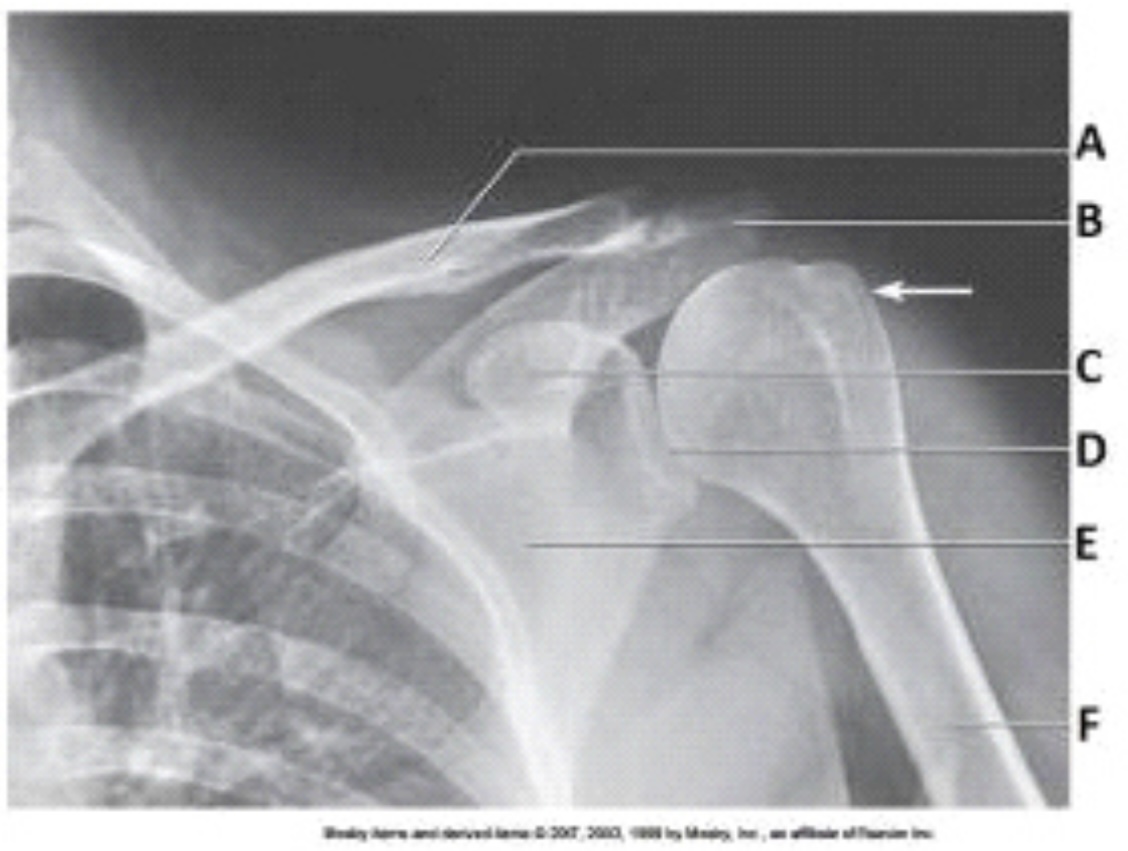

The projection in the image below was obtained with the arm positioned in:

external rotation.

Letter A in the image below labels the:

clavicle.

Letter B in the image below labels the:

acromion.

Letter C in the image below labels the:

coracoid process.

The white arrow in the image below points to the:

greater tubercle.

The glenoid of the scapula in the image below is labeled as letter:

D.